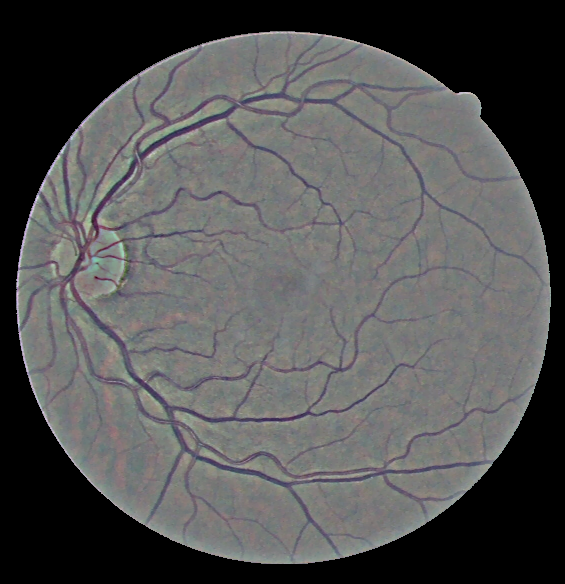

Raw fundus image and CLAHE applied

In the CLAHE method, there is significant improvement in contrast, because of which vasculature of the fundus images becomes very clear. But there are still some dark spots and blobs, showing uneven illumination. The method used in this project uses a global noise estimation based image decomposition method to divide the input image into three layers, i.e., the base, detail, and noise layers. Then the base layer is corrected in HSV space, detail layer is enhanced and then they are combined back. Noise layer is rejected.